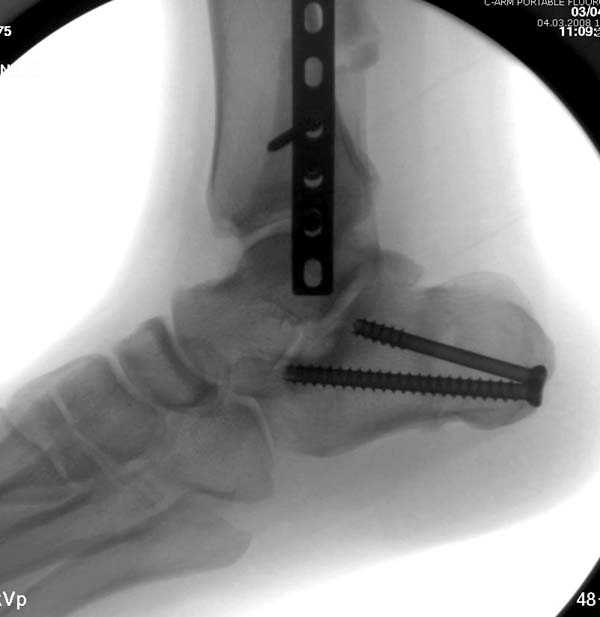

Здесь представлено решение похожей проблемы. Больной в течение года лечился консервативными мерами, и боли в голеностопе были основным показанием к операции.

Проведена обычная стандартная процедура по исправлению неудовлетворительного состояния голеностопного сустава, где кроме удлинения малоберцовой с применением compression tension device за проксимальный конец пластины, проведено замещение трикортикальным графтом из крыла, освобождение синдесмоза и медиальной щели от

фибротических масс с фиксацией.